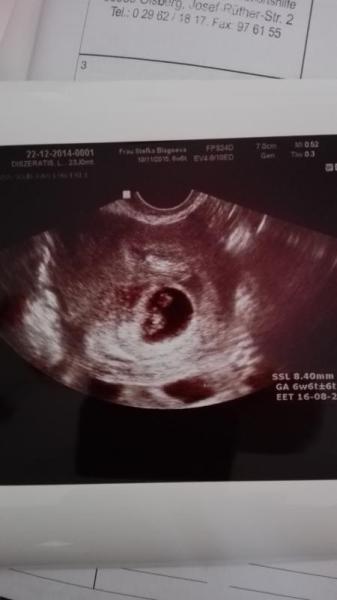

Hallo ihr Lieben War heute morgen beim Frauenarzt sie sagte mir das ich in der 7.ssw sei und ihr hattet recht alle sorge umsonst dem würmchen gehts gut hab sogar das schlagen sehen und der bluterguss ist wie durch ein Wunder weg wir sind so überglücklich hab sogar heute meinen mutterpass bekommen Sie sagte mir da ich ja schon 2 kaiserschnitte hatte und es auch diesmal einer wird das ich mich danach doch sterilisieren lassen solle da alle weiteren ss gefährlich werden würden hab ihr nur den vogel gezeigt was haltet ihr davon?? Und nun ein riesen lob an euch ich find das einfach wahnsinnig klasse das ihr hier den schwangeren so viel tipps und Erfahrungen gebt und ihnen in so vielen sachen mut macht ich danke euch dafür weiter so

Bild zu Zurück vom Frauenarzt....bild....und lob an euch - Schwanger - wer noch? Rund um die Schwangerschaft

Hallo, ich möchte dir als erstes sagen das man deine Daten lesen kann auf dem bild. Ansonsten ist wenn mit der Narbe alles okay ist es kein Problem noch einen 4. Ks zu machen. Hier kriegt eine demnächst sogar den 7 ks ,mir hat man nach dem jetzt gesagt 8 Kinder sollten wir nicht kriegen. Aber mein Narbe von Nummer 1 ist beim Versuch der natürlichen geburt nämlich fast gerissen ne std mehr und es wäre zu spät gewesen. Und man sollte mindestens 1 jahr warten bis man erneut ss wird. Lg nita

Ist das Bild von 2014?